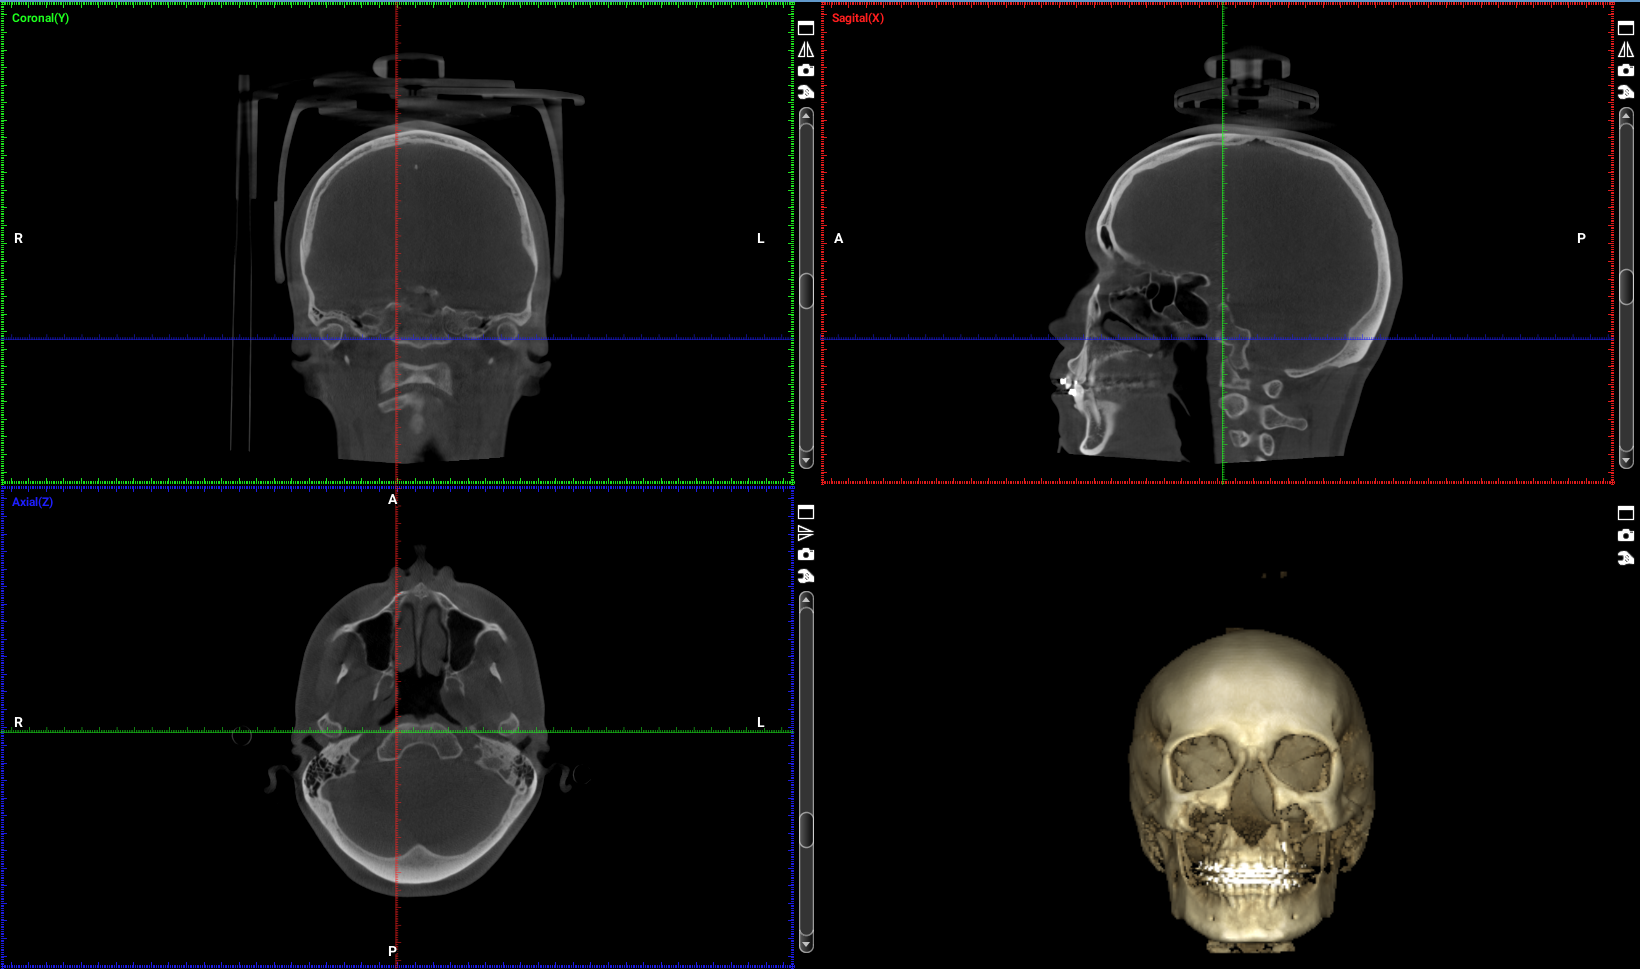

Importancia del campo de visión (FOV) en estudios CBCT

Uno de los aspectos más importantes —y a menudo desconocidos— en un estudio CBCT es la correcta elección del campo

El CBCT (Tomografía Computarizada de Haz Cónico) es una de las herramientas diagnósticas más importantes en la odontología actual. Su